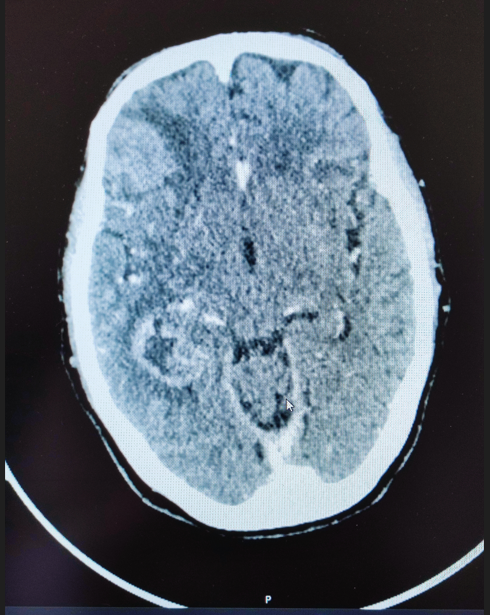

The patient underwent a neuronavigation-guided stereotactic biopsy without immediate complications. Postoperative imaging identified a small intratumoral hemorrhage without mass effect (Figure 2). Histopathological examination confirmed a diagnosis of high-grade glioma consistent with an IDH-wild-type glioblastoma. Treatment was promptly initiated with dexamethasone to reduce peritumoral edema and levetiracetam for seizure prophylaxis.

Figure 2 Stereotactic biopsy with minor hemorrhage.